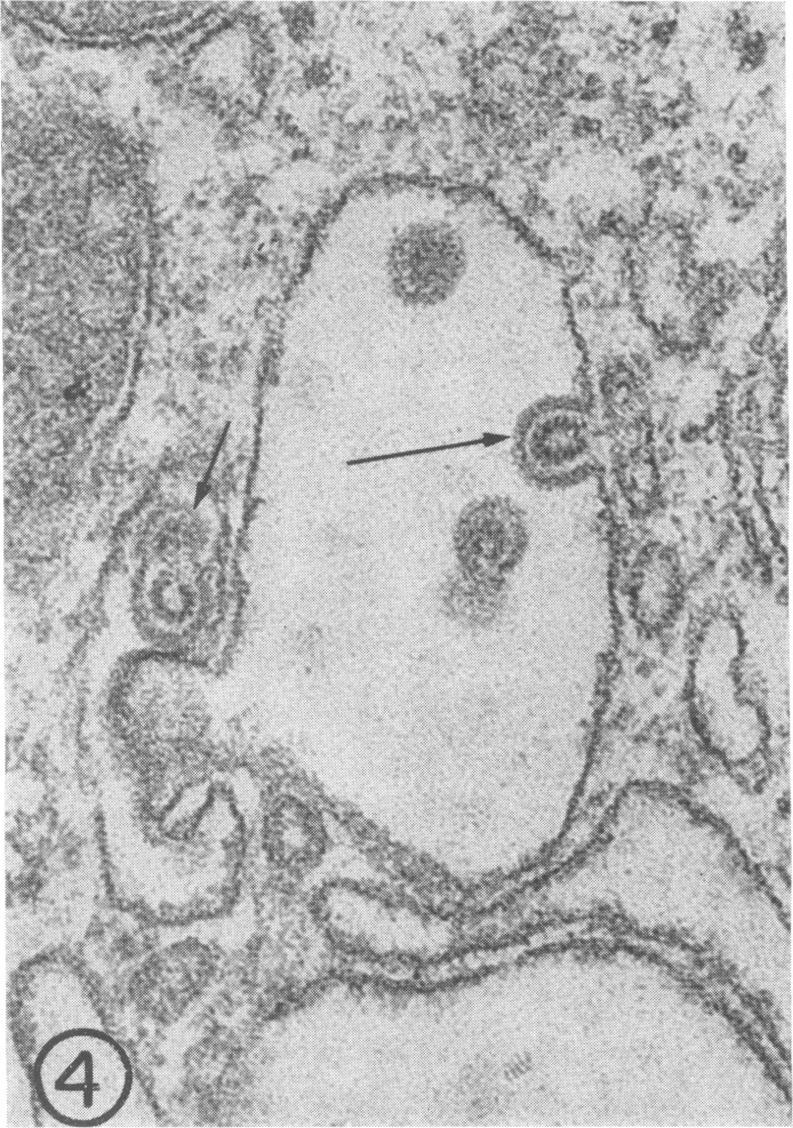

Sequential effects of rubella virus infection in BHK-21 cells were studied by electron microscopy of thin sections of control and infected cells, 2 to 7 days after infection. Vacuolization of cytoplasm in Golgi areas apparently preceded budding of virions from vacuole membranes and involvement of the endoplasmic reticulum. Newly formed endoplasmic reticulum cisternae encircled and segregated virionforming vacuoles together with other cellular elements. Large vacuolar complexes with numerous virus particles developed, and virus release from these areas occurred with disruption at the cell periphery. The viral particles, with a mean diameter of about 56 nm, consisted of an electron-dense core surrounded by a less dense capsid, enveloped by a typical unit membrane derived from the vacuole membrane.

通过对感染后2至7天的对照细胞和感染细胞的超薄切片进行电子显微镜观察,研究了风疹病毒在BHK - 21细胞中的连续效应。高尔基体区域细胞质的空泡化显然先于病毒粒子从液泡膜出芽以及内质网的参与。新形成的内质网池与其他细胞成分一起包围并分隔形成病毒粒子的液泡。形成了含有大量病毒颗粒的大液泡复合体,病毒从这些区域释放时细胞周边会发生破裂。病毒粒子的平均直径约为56纳米,由一个电子致密的核心和一个密度较低的衣壳组成,被源自液泡膜的典型单位膜包裹。